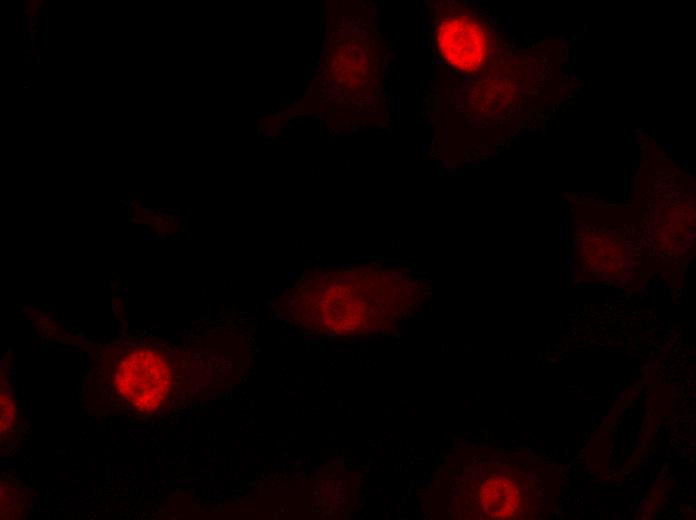

BRCA1M1138

Mitochondria

(Mitotracker)